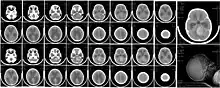

CT scan, showing a tumorous mass in the posterior fossa, giving rise to obstructive hydrocephalus, in a six-year-old girl | |